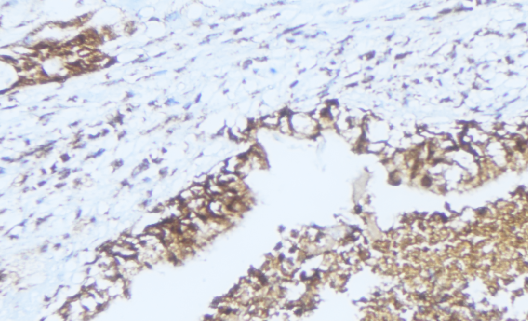

IHC (Immunohistochemistry)

(AAA325050 at 1/100 staining Human lung cancer tissue by IHC-P. The sample was formaldehyde fixed and a heat mediated antigen retrieval step in citrate buffer was performed. The sample was then blocked and incubated with the antibody for 1.5 hours at 22 degree C. An HRP conjugated goat anti-rabbit antibody was used as the secondary.)